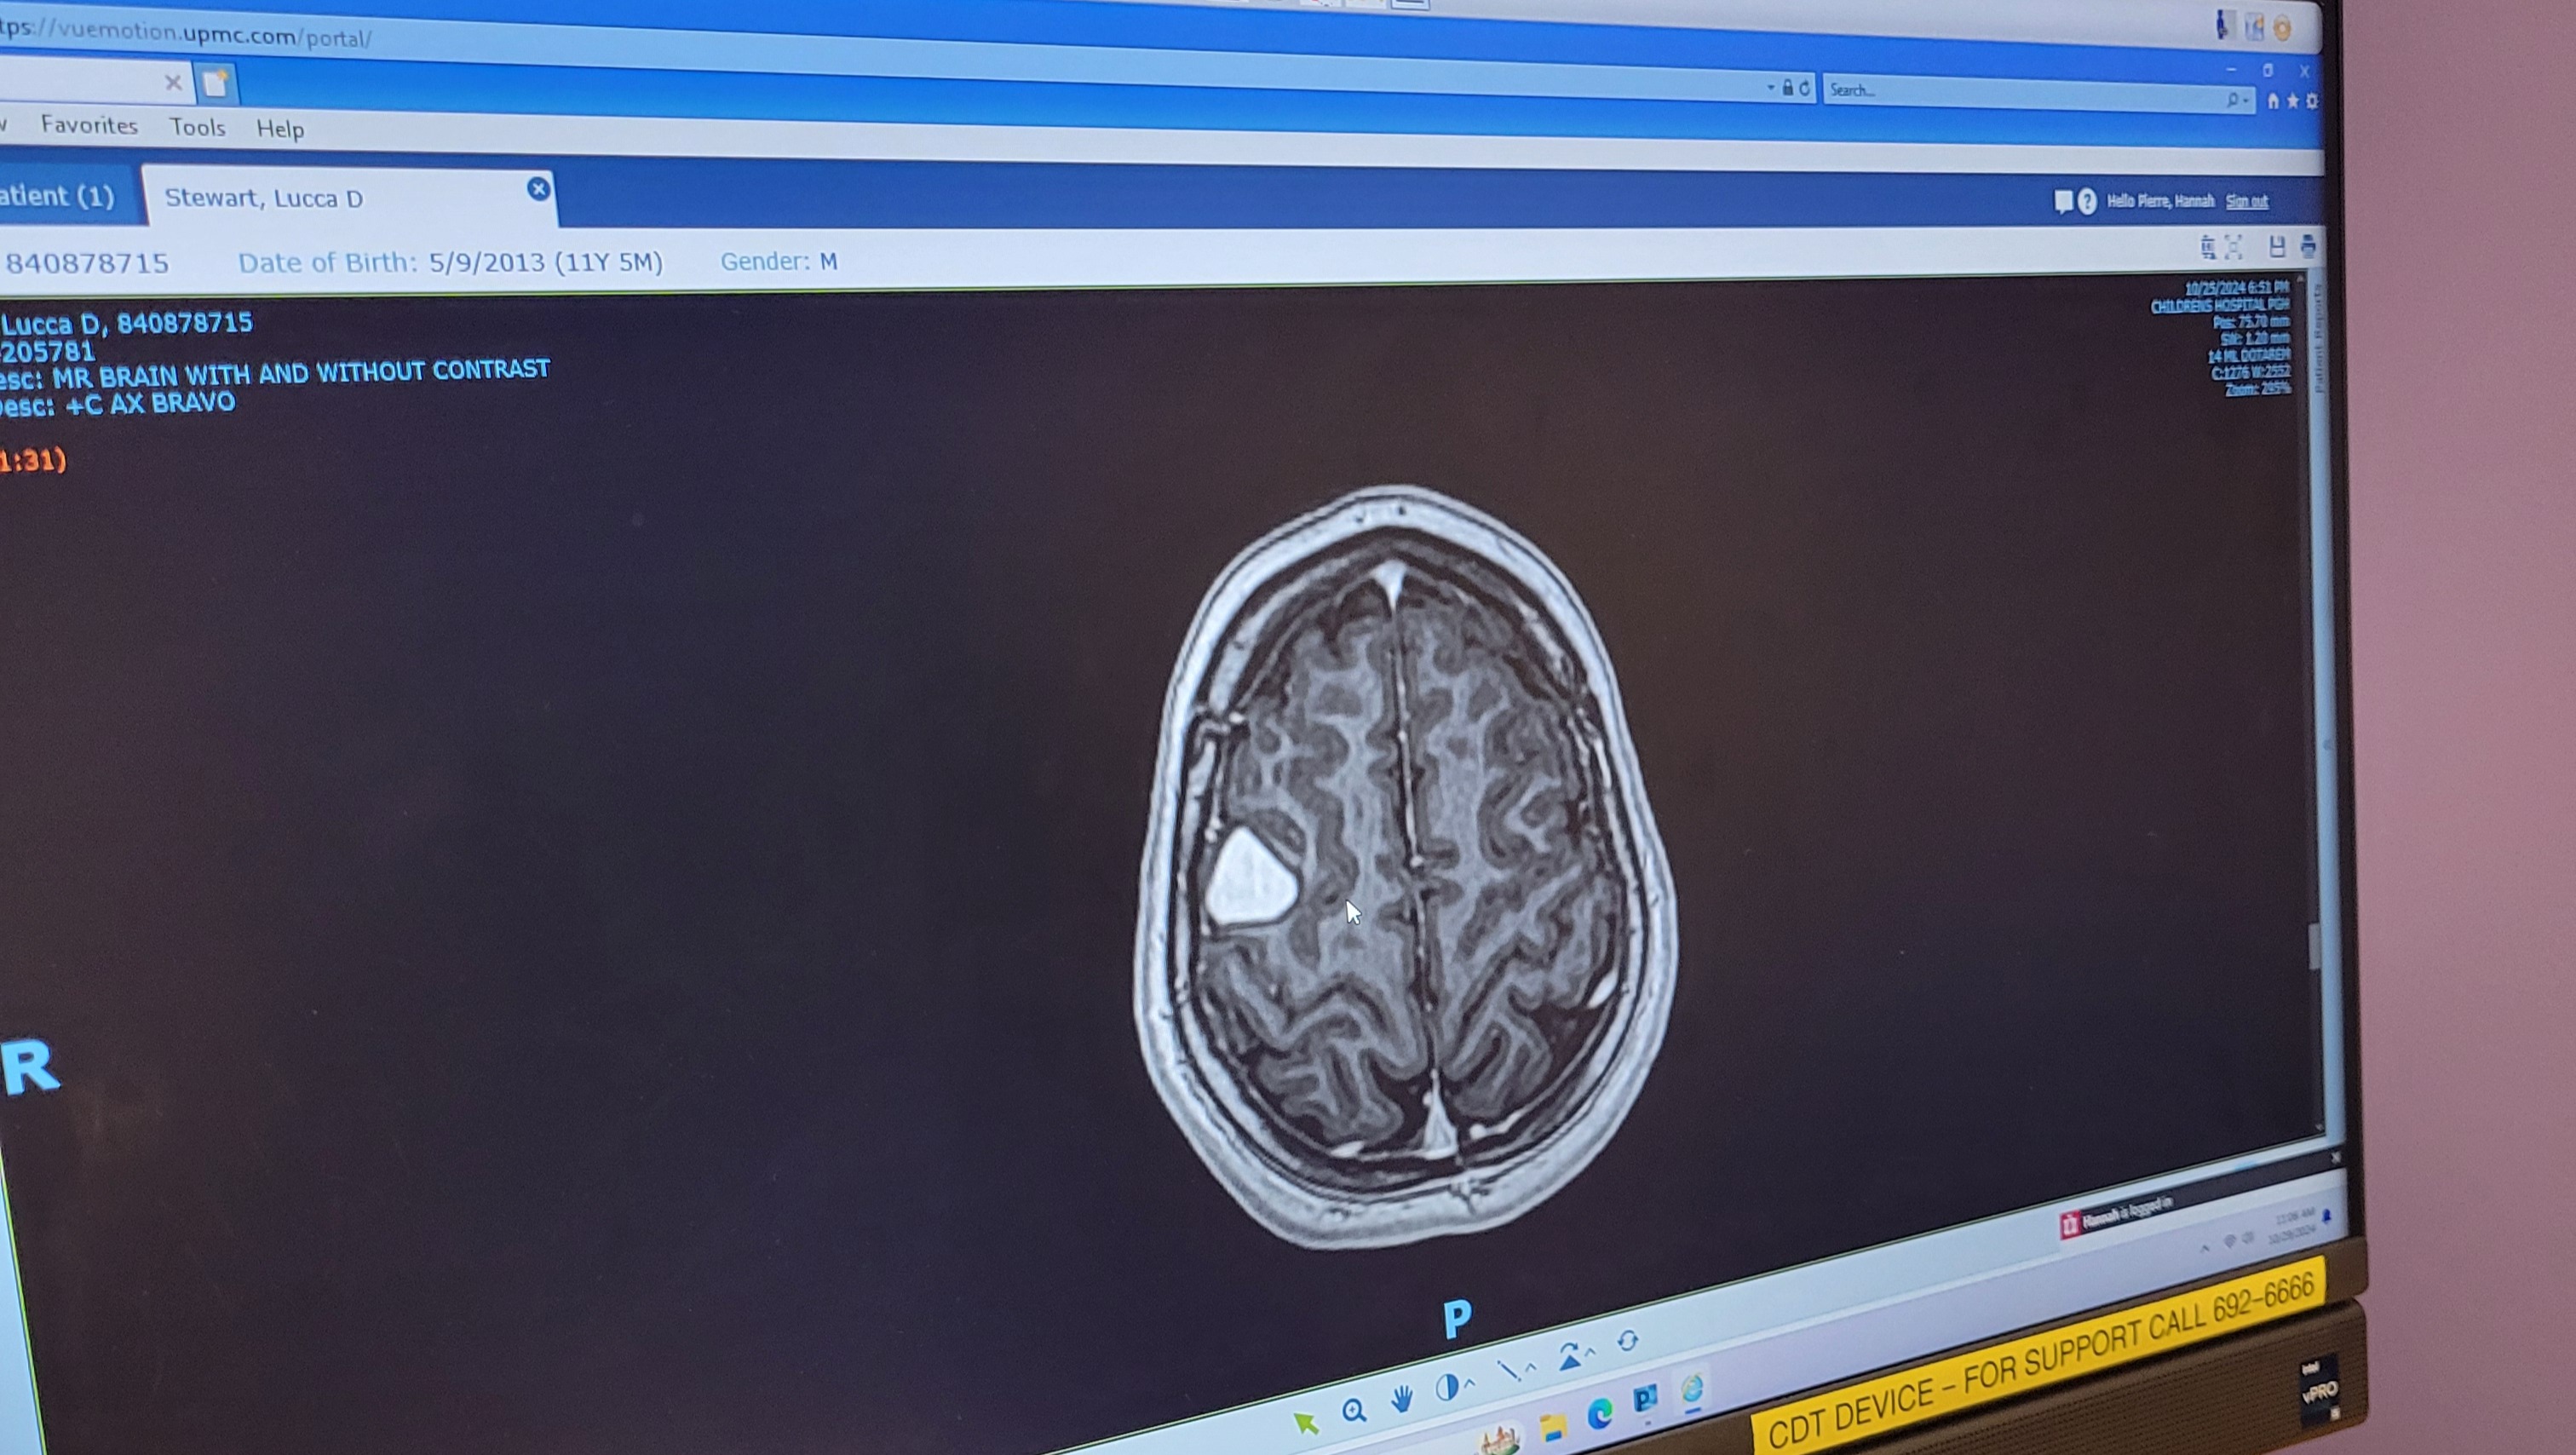

As most don't know, he was diagnosed with a brain tumor not very long ago.

Lucca originally was scheduled for removal and biopsy December 17th but he really wanted to be home for Christmas. Surgery date is now scheduled for January 14th at Childrens Hospital of Philadelphia .